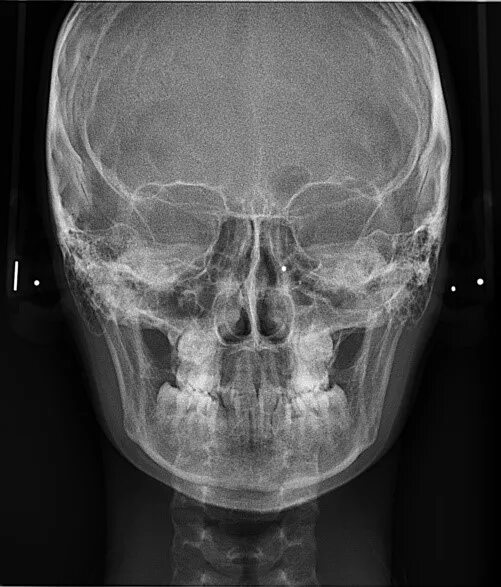

Снимок черепа в прямой проекции